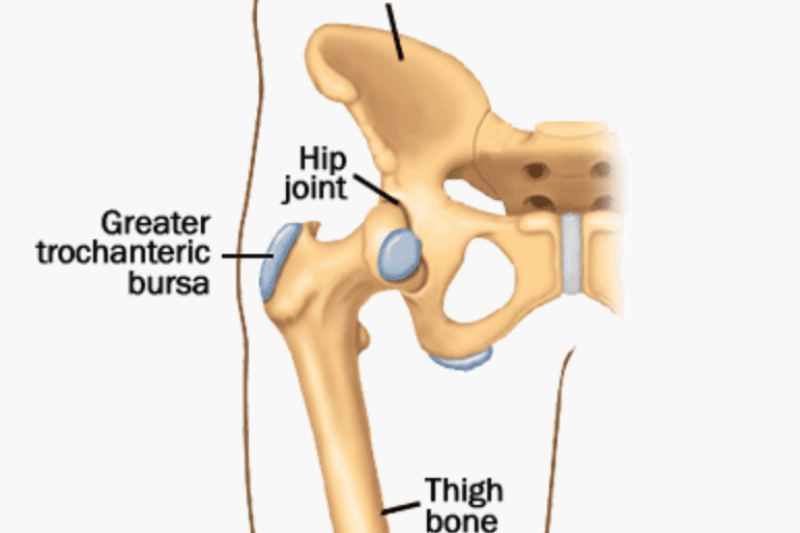

What is Pseudogout “false gout”? Calcium Pyrophosphate Deposition (CPPD) also known as Pseudogout, is a joint problem caused by crystals of calcium salt called Pyrophosphate that are deposited …